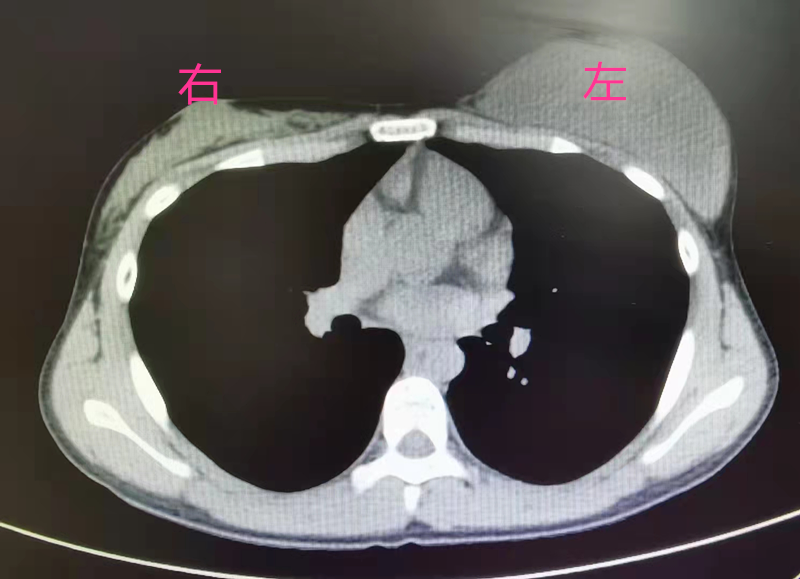

患者小雪(化名)家住汉川,一年半前,她自觉左侧胸部逐渐增大,正处于青春期的她以为是正常的生长发育就一直没有放到心上。春节期间,小雪外出打工的父母回汉川过年,妈妈聂女士在洗澡时发现女儿左右胸部大小差别巨大,感觉不对劲的聂女士赶紧带着小雪去了医院,在当地医院经乳腺彩超提示,左侧乳腺实质病灶有两个,大的约有9.2×3.0×8.6㎝,小的约有0.7×0.3㎝,怀疑恶性肿瘤可能。

为了进一步确诊和治疗,聂女士带着小雪来到了91porn (湖北省中山医院)甲乳外科。接诊医生发现,小雪左侧胸部如成人大小,犹如乳房假体在内,右侧胸部还尚未发育,进一步完善相关检查后,建议小雪手术治疗。